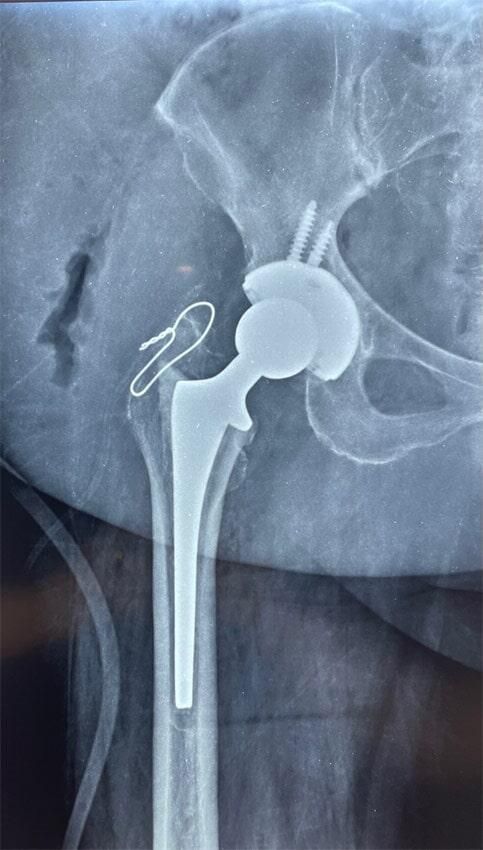

ButtonARTROUPN - Reemplazo total de cadera

ButtonARTROUPN - reemplazo de cadera